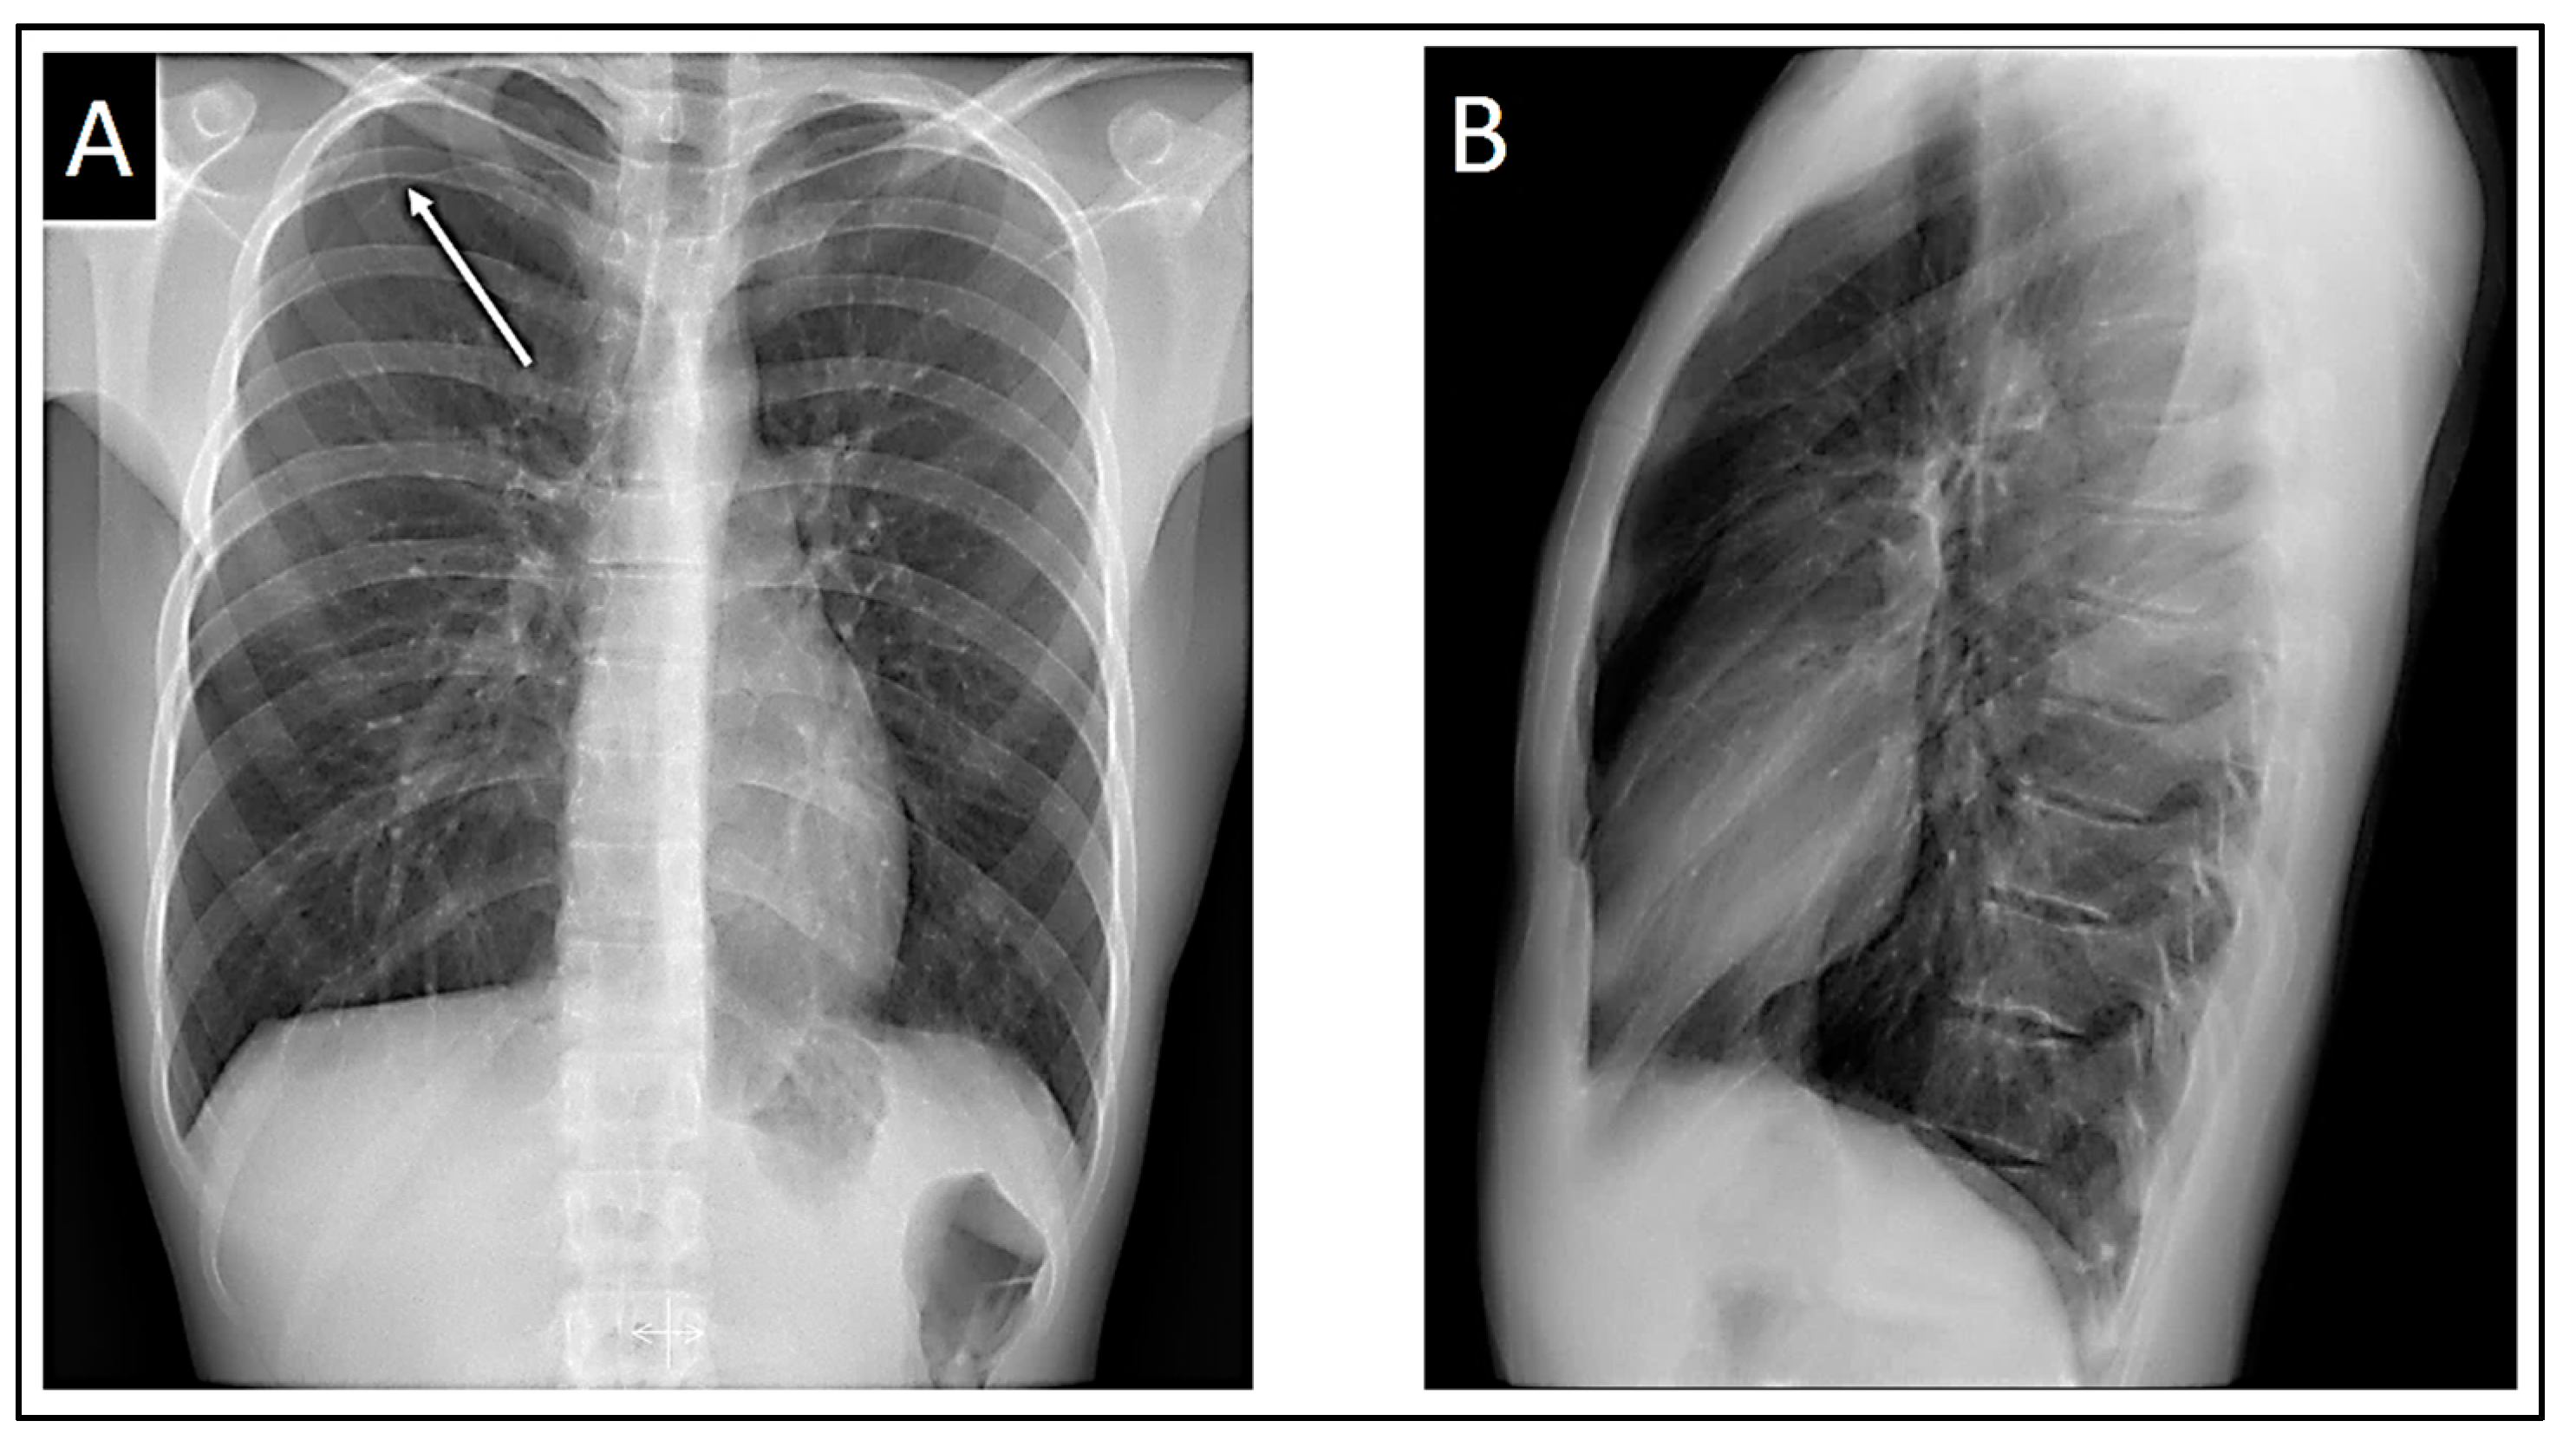

Both the chest X-ray and electrocardiogram were repeated at 48 hours, revealing an improvement in the pneumothorax with a halving of the pleural space volume, alongside the disappearance of Brugada patterns displaying appropriate morphology for identification. In lead V1, a tendency toward β angle formation persists, while in V2, a 1 mm elevation of the J point is evident with T-wave morphology tending to notch at its center. Nonetheless, no curves exhibit morphology of sufficient quality to suggest a pattern visually.

Figure 6. At 48 hours. A: Posteroanterior chest X-ray demonstrating improvement of the pneumothorax. B: Lateral chest X-ray still demonstrating absence of cardiac compression due to the patient’s thoracic morphology. C: Loss of Brugada patterns with the required quality for consideration.